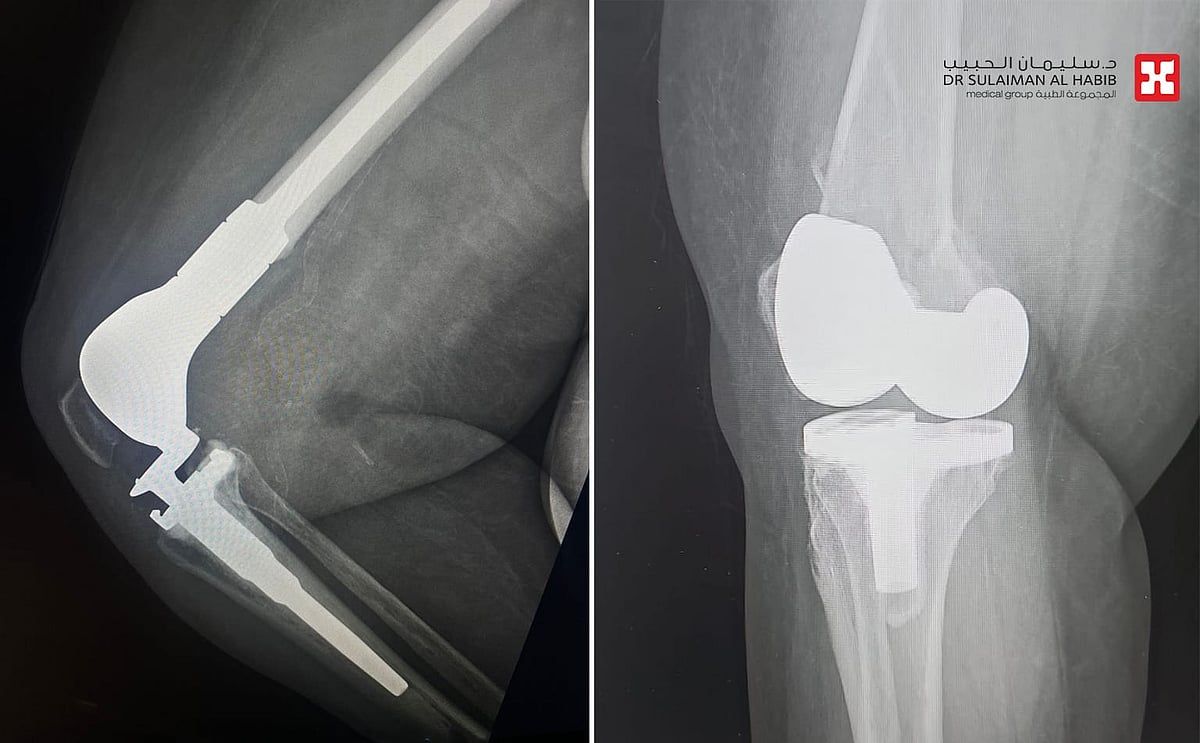

شهد مستشفى الدكتور سليمان الحبيب بالسويدي، إجراء عملية متقدمة لاستبدال الجزء السفلي من عظمة الفخذ Distal Femoral Replacement, DFR لسيدة تبلغ من العمر"80" عاماً، كانت قد خضعت لعملية استبدال مفصل ركبة قبل عامين، وتعرضت مؤخراً لحادث منزلي عرضي، نتج عنه كسر في أسفل عظمة الفخذ، وعانت من أعراض حادة. ذكر ذلك د. رغيد شبو استشاري جراحة العظام والإصابات واستبدال المفاصل رئيس الفريق الطبي المعالج.

الذي قال أن السيدة حضرت إلى المستشفى وهي تشتكي من آلام حادة وتورم بالطرف السفلي الأيمن، مع عدم القدرة على الحركة والتحمل، إضافة إلى أمراض مزمنة كالشريان التاجي وداء السكري وارتفاع ضغط الدم، وخضعت لفحوصات دقيقة، حيث أظهرت صور الأشعة الطبية كسراً في نهاية عظم الفخذ حول المفصل الصناعي، وتبين عدم قابلية الكسر للتثبيت بالصفائح أو البراغي، بالنظر إلى هشاشة عظام المراجعة وتقدم عمرها، فتم تبني خطة علاجية تناسب الحالة، وأجريت لها عملية جراحية تم فيها استبدال الجزء السفلي من عظمة الفخذ، في تدخل جراحي استمر لـ"4" ساعات، وتكللت ولله الحمد بالنجاح التام، ونقلت المراجعة إلى جناح التنويم.